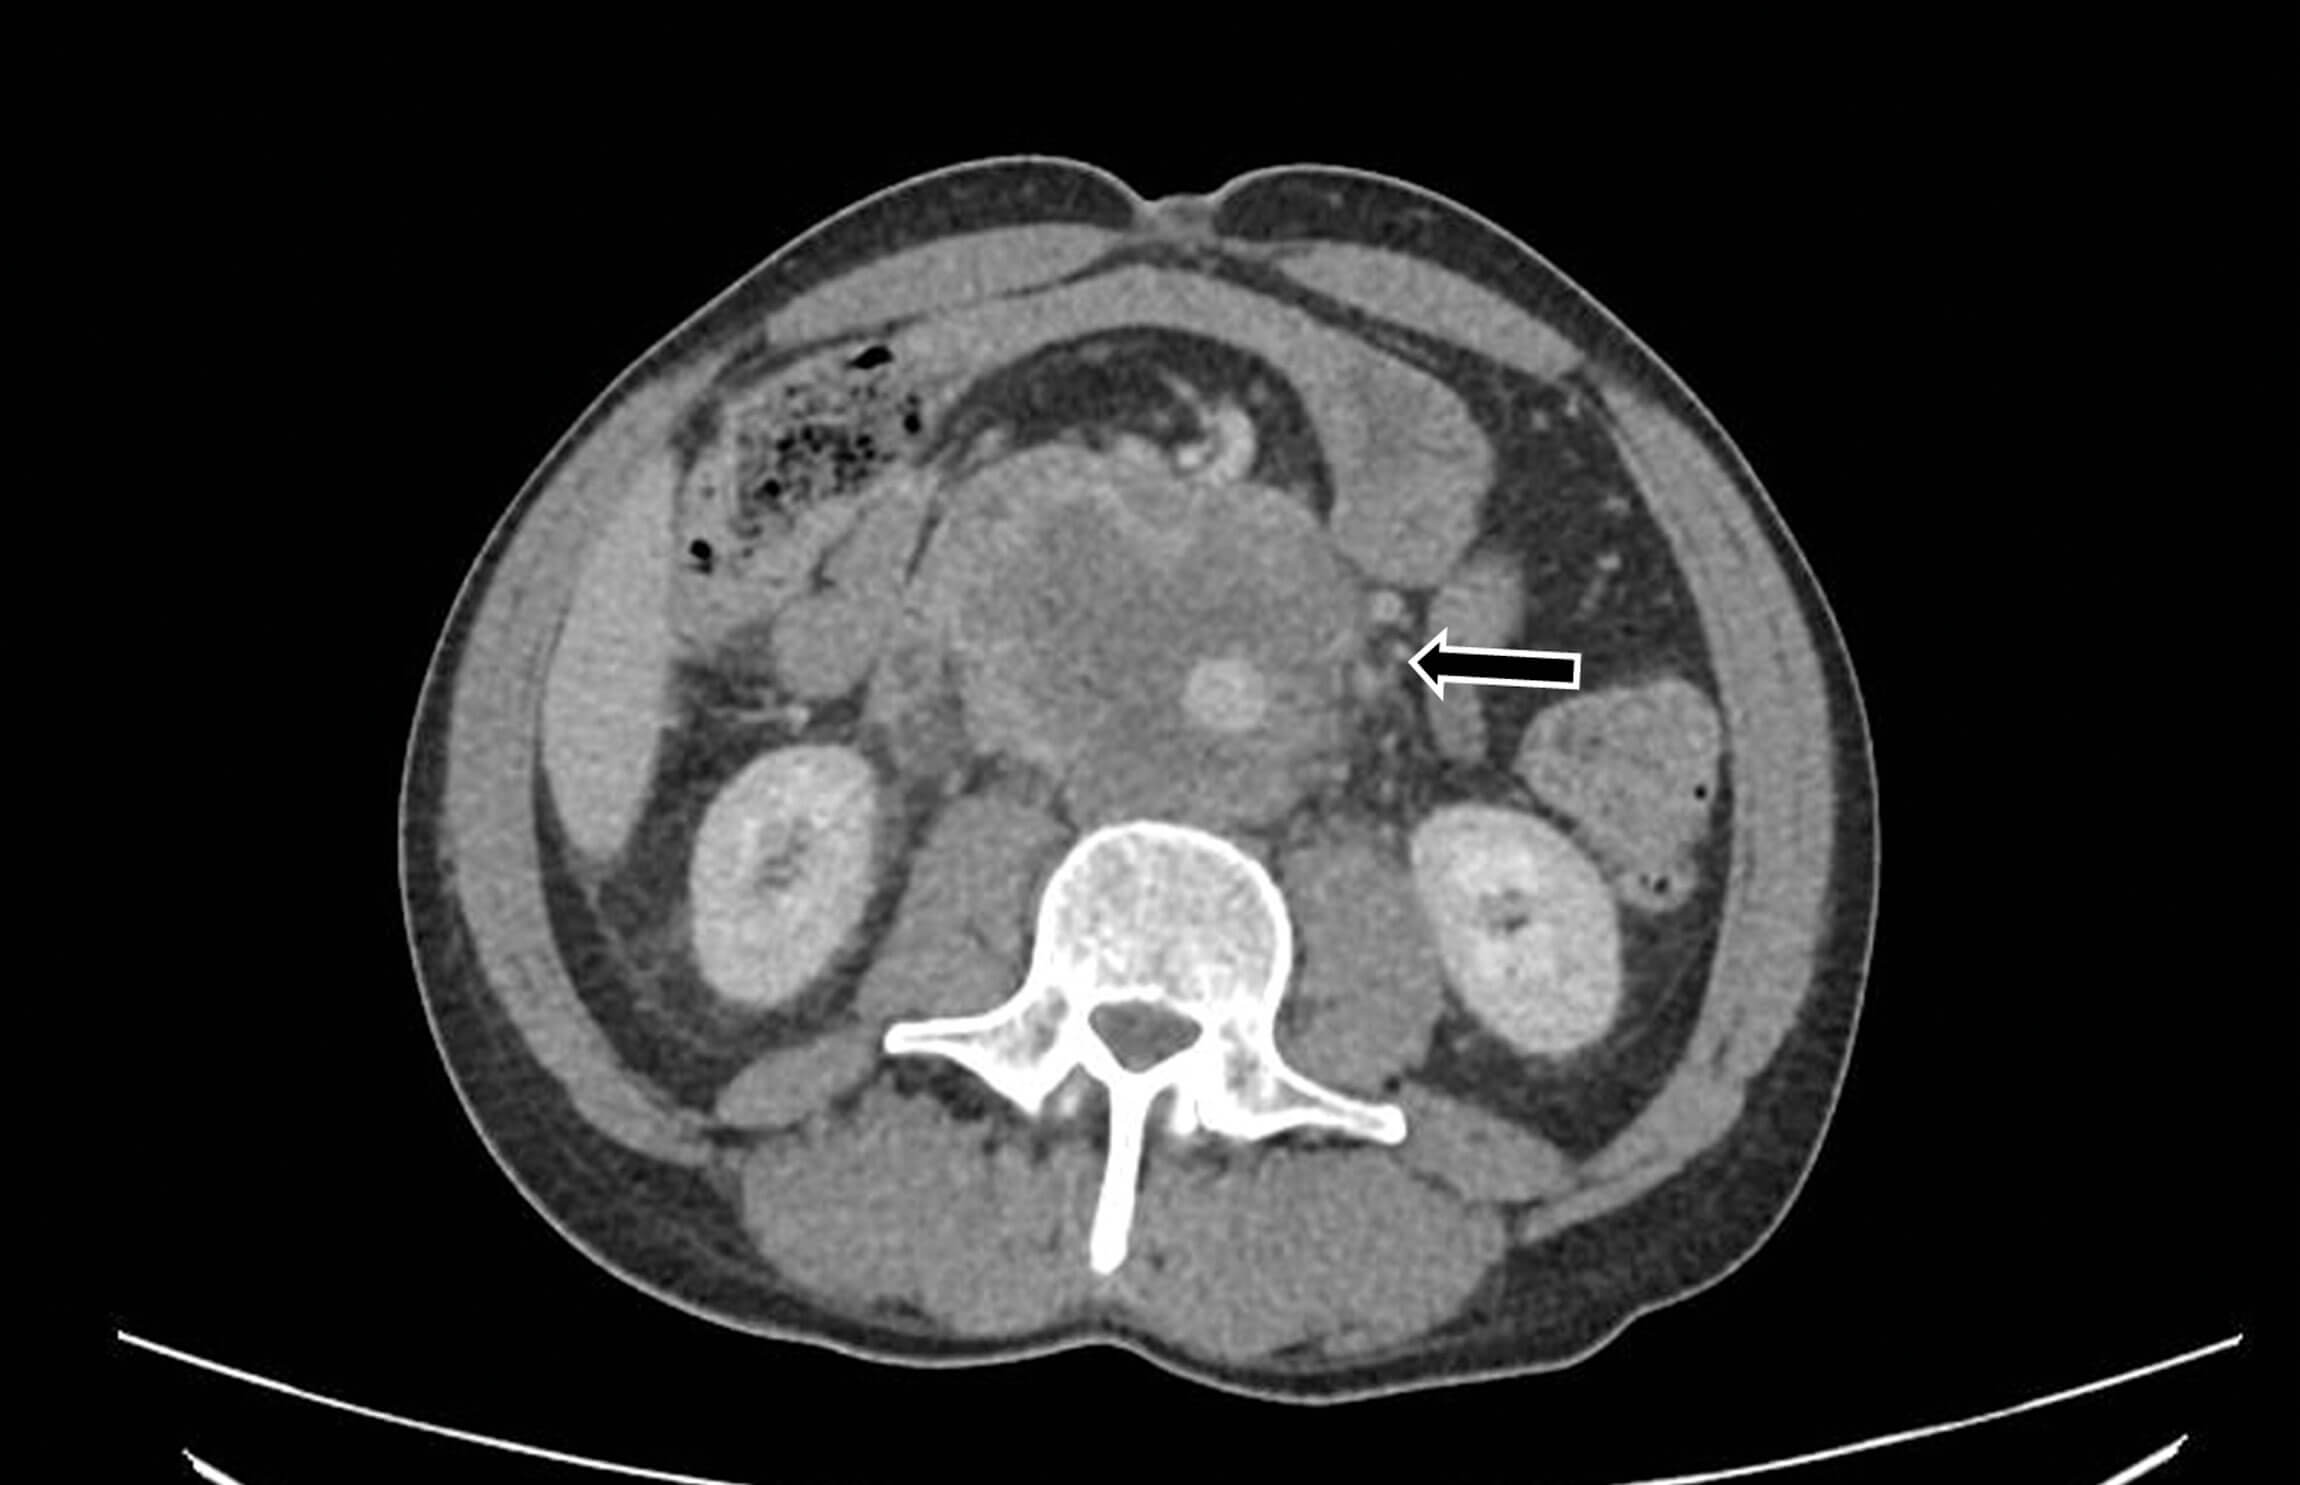

A 51-year-old man presented to A&E with symptoms of lethargy, weight loss, decreased appetite and abdominal pain for one month. He had been treated for prostatitis with antibiotics by his GP without improvement in symptoms. He was examined by the medical team and consultant who found no testicular abnormality. His chest x-ray showed cannonball metastases, and a CT found a large retroperitoneal mass encasing the pulmonary vein, right hydronephrosis, liver metastases and subcarinal lymph nodes (Figure 6).

Figure 6: Large retroperitoneal mass encasing the great vessels.